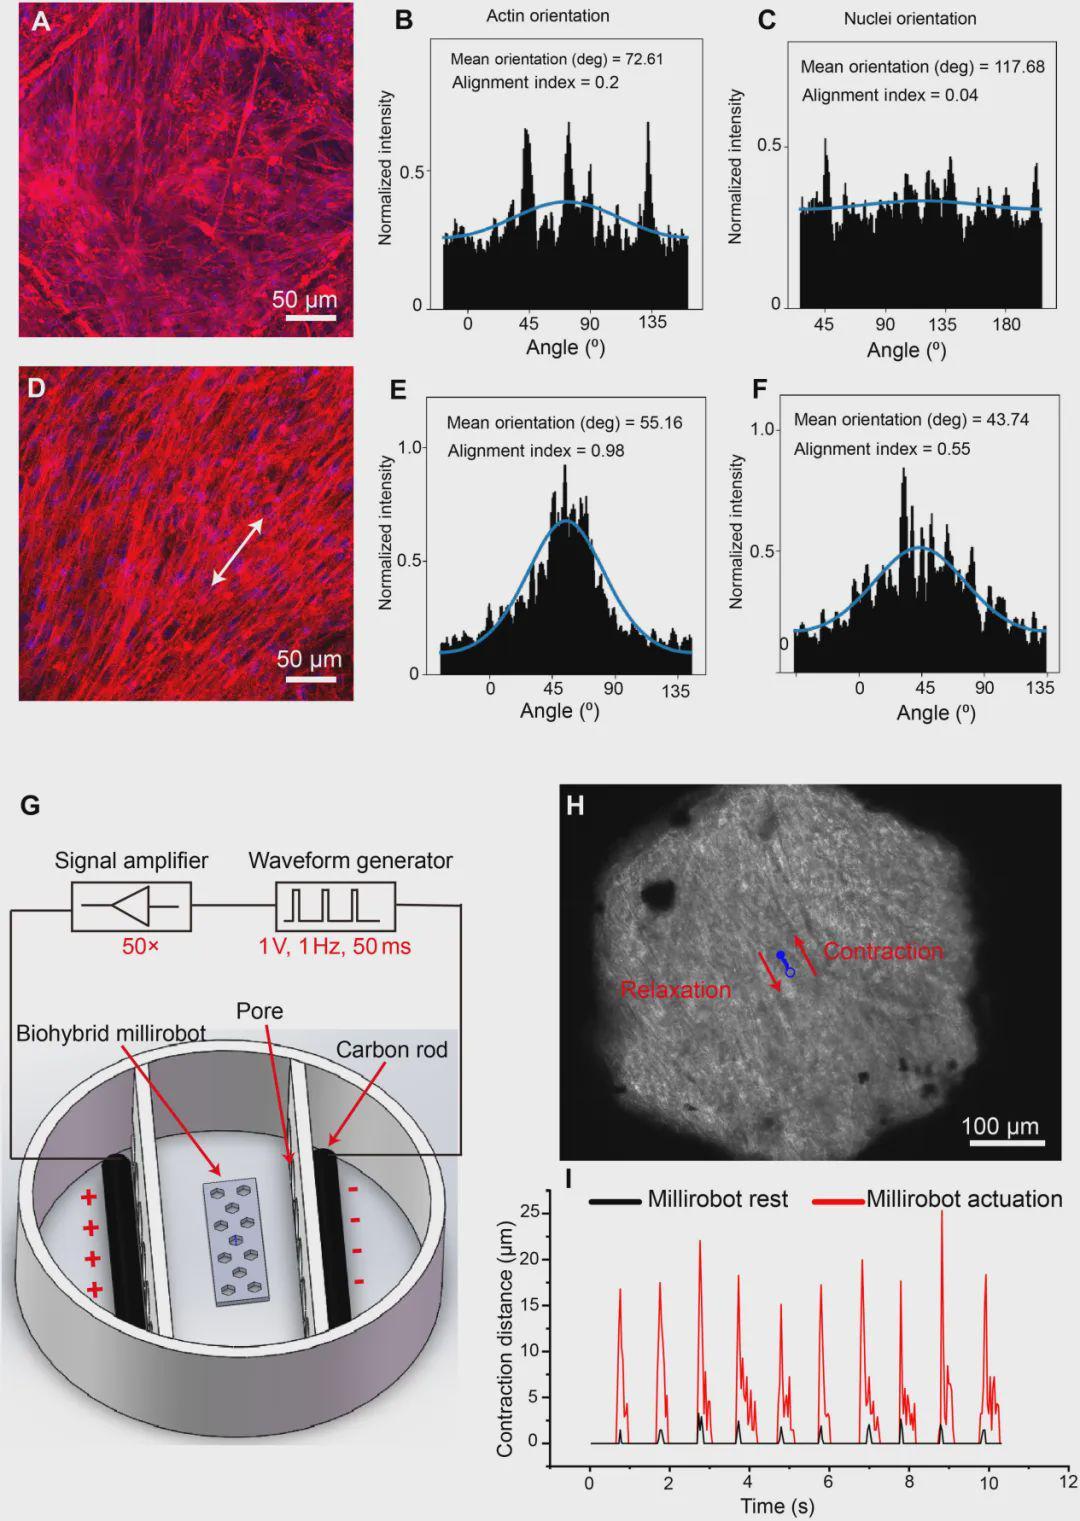

▍体内导航与递送:穿越蜿蜒胆管的细胞“特快专列”

细胞功能增强了,如何精准送达复杂深处的病灶?

团队开发了一套集成机器人平台,将磁驱系统与超声成像结合,实现了机器人的实时影像引导与闭环控制。

在离体猪肝模型中的演示令人印象深刻。

2D细胞片机器人(尺寸:6.4×2×0.2 mm)在旋转磁场驱动下,以0.24 mm/s的速度在胆管中实现波动爬行。它能自适应管道尺寸变化,从3mm宽的区域进入仅0.5mm的狭窄段(远超传统内窥镜可达范围),形状从倒C形变为正弦波形。

3D水凝胶机器人(更厚,约1.1mm)也能在1.5mm以上管道中运动,但在1.1mm处受阻,速度较慢(0.08 mm/s)。

送达后,细胞可迁移。将机器人放置于培养皿或细胞层上,其携带的细胞能有效迁移、铺展并增殖,存活率>95%,显示出良好的组织整合潜力。

此外,机器人还能作为主动贴片粘附在离体肌肉组织表面,通过磁驱收缩对深层组织(深度达5mm)施加机械应力,展示了其用于力学治疗的潜力。